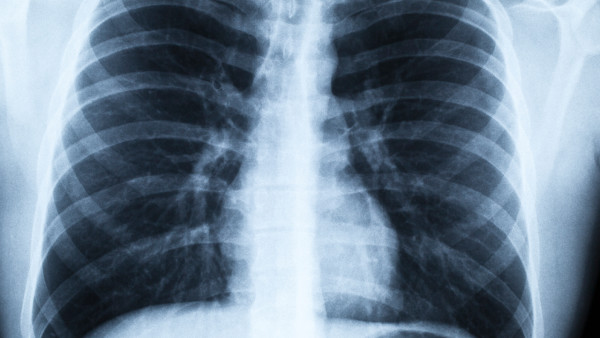

肺结核是由于结核分歧杆菌引起的慢性传染病,主要通过呼吸道传播、消化道传播等途径进行传播。如果只是单纯的吃了夹过肺结核病人食物,并没有出现其他不适症状,这种情况一般是不会引起疾病的发生的。因为人体内存在针对结核菌素的抗体,可以起到抵抗结核菌的作用,所以是不会发生传染的情况。

但是如果在吃饭的过程中,不小心咬破了嘴唇或者牙龈部位,此时就有可能会导致唾液中的结核菌进入体内,从而引发疾病的发生。建议患者可以在医生指导下使用利福平胶囊、异烟肼片等药物进行抗结核治疗。同时还要注意饮食卫生,避免与他人共用餐具,以免造成交叉感染。